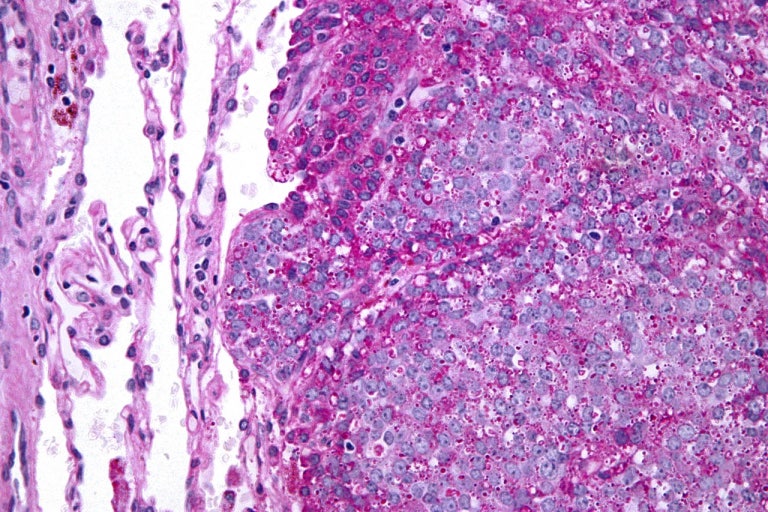

특히 연부조직육종, 골반 주변 종양 등은

초기 증상이 엉덩이·허벅지 통증으로 시작되는 경우가 보고됩니다.

이들은 X-ray로 잘 드러나지 않아

MRI·CT 같은 정밀검사가 중요합니다.